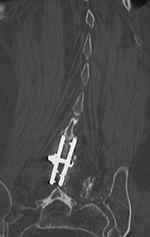

| 85 year-old woman. These images show respectively an AP radiograph of an ILIF at L4-5, an axial CT image of the ILIF, and two coronal reformatted CT images of the ILIF. There is a donar bone plug held in place by the interspinous fixation plate (clamp). |